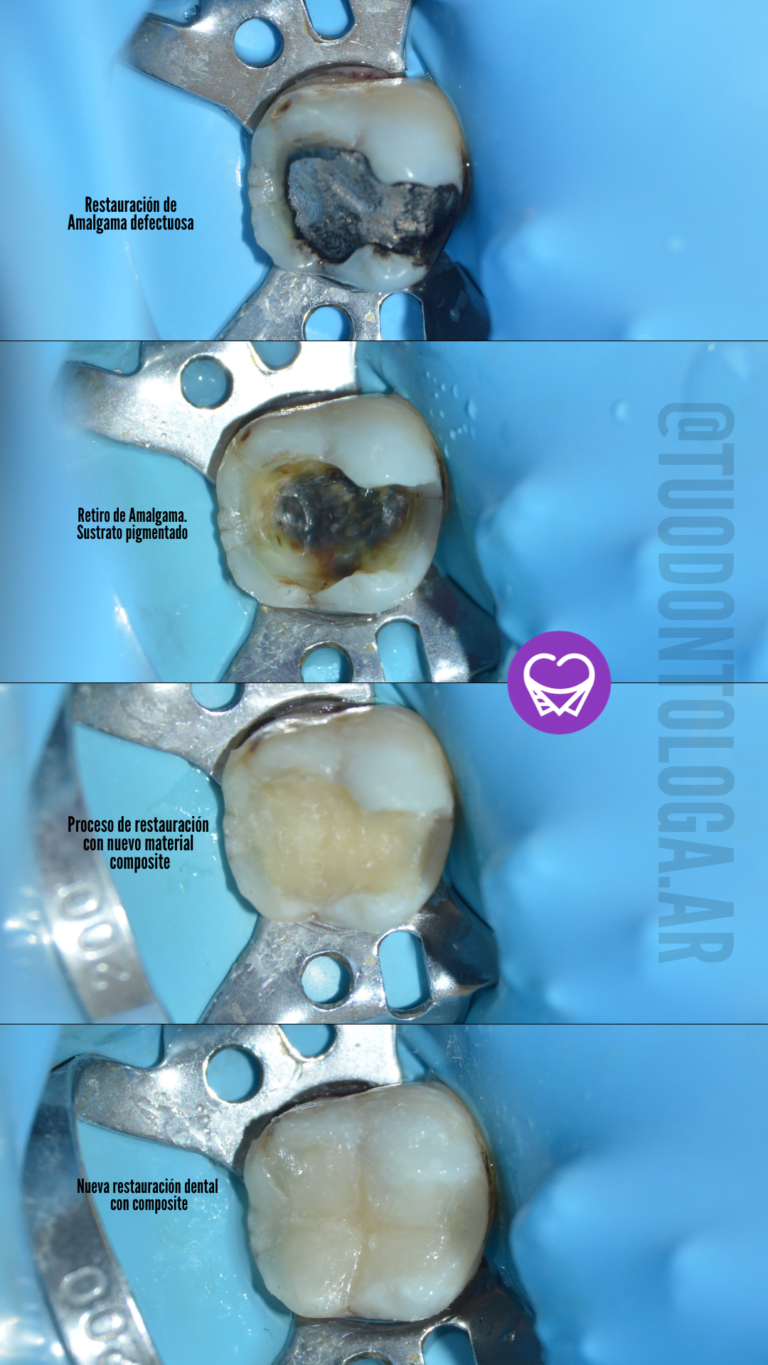

Eliminación y cambio de Amalgamas​

Las amalgamas dentales han sido utilizadas durante muchos años por su durabilidad y bajo costo para rellenar las cavidades de los dientes. No obstante, presentan algunos inconvenientes, como la falta de adhesión al diente, lo que produce una retención mecánica y puede provocar fisuras y fracturas a largo plazo. Además, las amalgamas contienen mercurio, un metal que puede resultar tóxico en altas concentraciones.

Por esta razón, muchos pacientes optan por reemplazar las amalgamas por materiales más seguros y estéticos, como las incrustaciones cerámicas y los composites directos. Las incrustaciones cerámicas son piezas de cerámica a medida que se ajustan perfectamente al diente para restaurar su forma y función. Además, son altamente resistentes y duraderas.

Por otro lado, los composites directos son materiales de resina que se colocan en la cavidad del diente y se moldean para restaurar su forma y función. Además de ser altamente estéticos, ya que pueden adaptarse al color del diente natural, se adhieren químicamente al diente, lo que reduce el riesgo de fisuras y fracturas.